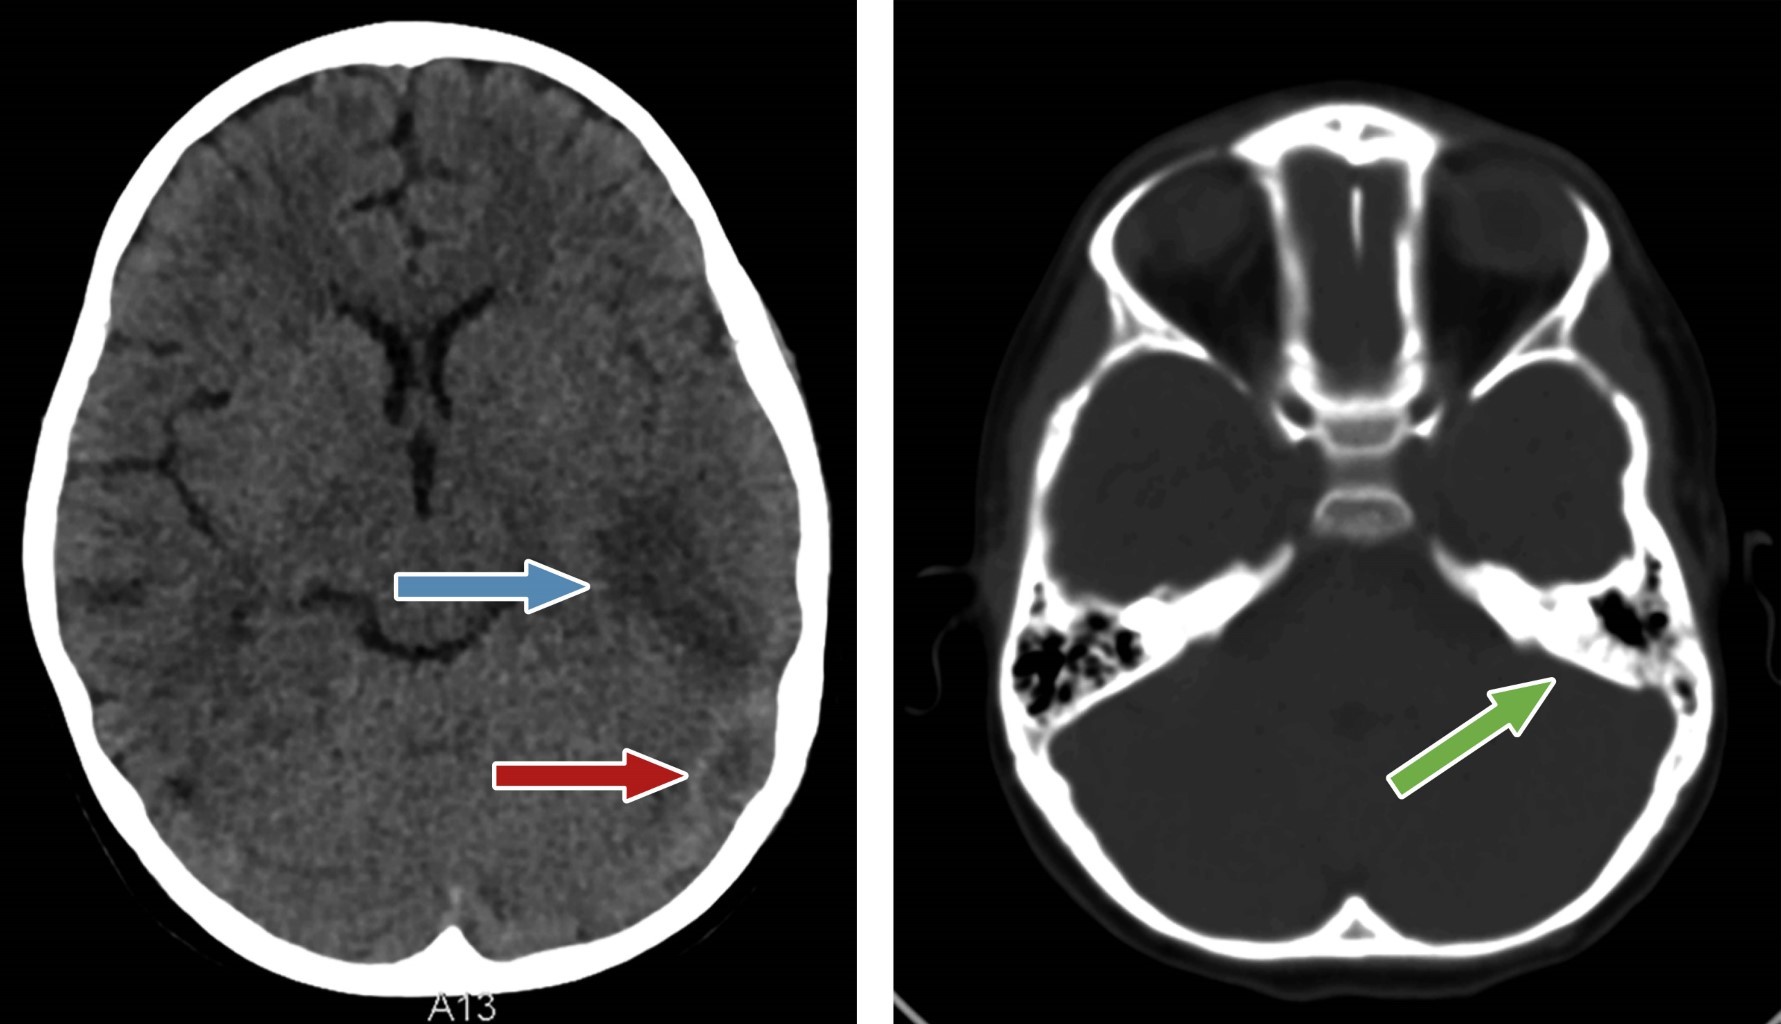

Con base en estos hallazgos, se agregó a la terapéutica heparina de bajo peso molecular una dosis estándar de 1 UI/kg dos veces al día para tratar la trombosis del seno venoso. Después de 25 días de haber recibido antibiótico vía endovenosa, la paciente fue intervenida quirúrgicamente, realizándole craniotomía y drenaje de la secreción purulenta, así como lavados con amikacina intratecal, con resultados favorables. Recibió antibióticos durante cuatro semanas y heparina de bajo peso molecular, sin nuevos eventos convulsivos ni deterioro clínico. Previo al alta, se realizó una tomografía cerebral de control, con buena resolución del absceso (Figura 4).

Figura 4